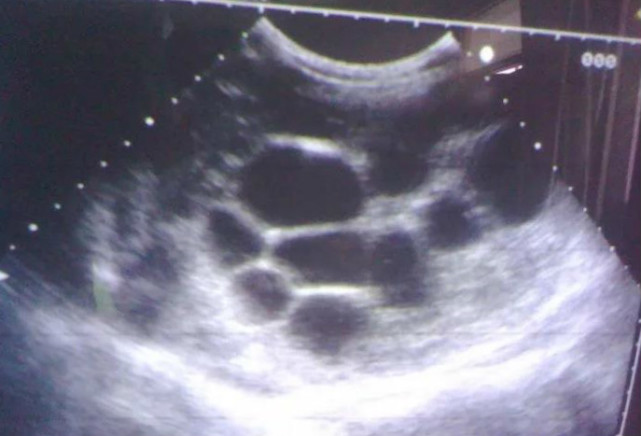

B型超声对北京犬肝、脾、肾、膀胱的诊断研究

5、超声检查:从影像学角度检查狗狗的内脏是否存在形态上的改变和功能上的异常,例如心脏瓣膜的闭合是否

做B超对于检查肝脏病变有没有作用?